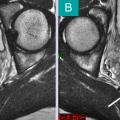

Syndrome douloureux régional complexe

SYNDROME DOULOUREUX REGIONAL COMPLEXE

GONALGIE

Image